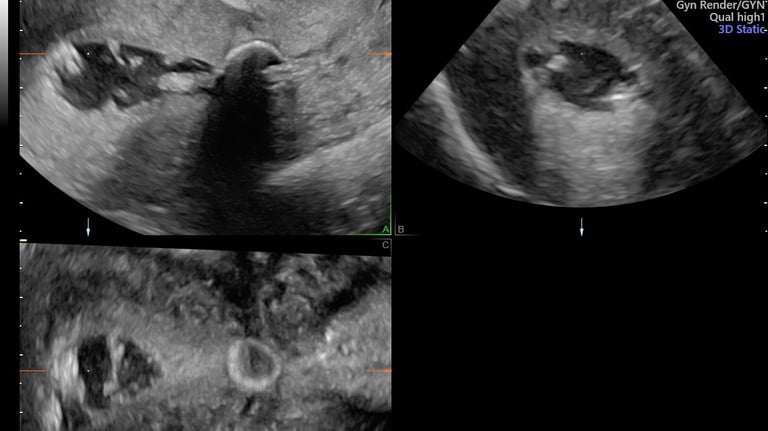

ecografía morfológica primer trimestre (genética y más)

12 - 14 semanas